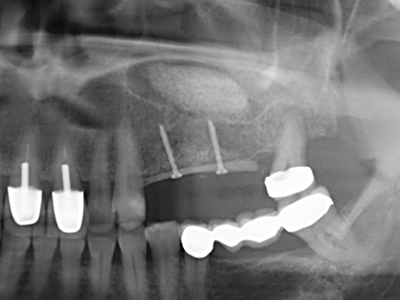

La piezochirurgia presenta altri vantaggi per quanto riguarda la raccolta di blocchi ossei. Oltre all'elevata precisione dell'osteotomia appena descritta, l'utilizzo di puntine per sega molto sottili permette di minimizzare in maniera significativa la perdita di materiale. È molto probabile che si verifichi una maggiore perdita di materiale durante la raccolta utilizzando puntine di strumenti più spessi, in particolare delle frese Lindemann (Lakshmiganthan, Gokulanathan et al. 2012). La separazione basale, necessaria in particolare per i trapianti di blocchi nella zona retromolare, viene semplificata grazie a seghe specificatamente progettate di forma rettangolare; di conseguenza la piezochirurgia è considerata una procedura precisa, semplice e sicura per la raccolta di blocchi di osso nella zona retromolare (Happe 2007) (figg. 1-12).